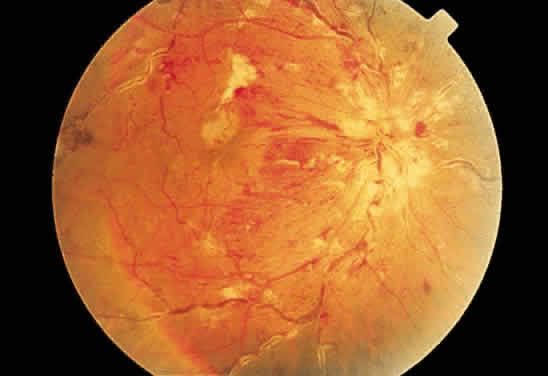

Cotton-wool spots are observed mainly in the posterior pole of the retina (Fig.23) The reason for this geographic restriction is not clear. Occlusion of

the most superficial radially oriented peripapillary capillaries (confined

in distribution to the posterior pole) has been implicated in the

pathogenesis of cotton-wool spots.9 It is also possible that nerve fiber infarcts in the periphery are not

visualized because there is insufficient inspissated axoplasmic material

in this location.  Fig. 23. Multiple cotton-wool spots along with retinal hemorrhages in a superior

temporal branch retinal vein occlusion. Fig. 23. Multiple cotton-wool spots along with retinal hemorrhages in a superior

temporal branch retinal vein occlusion.